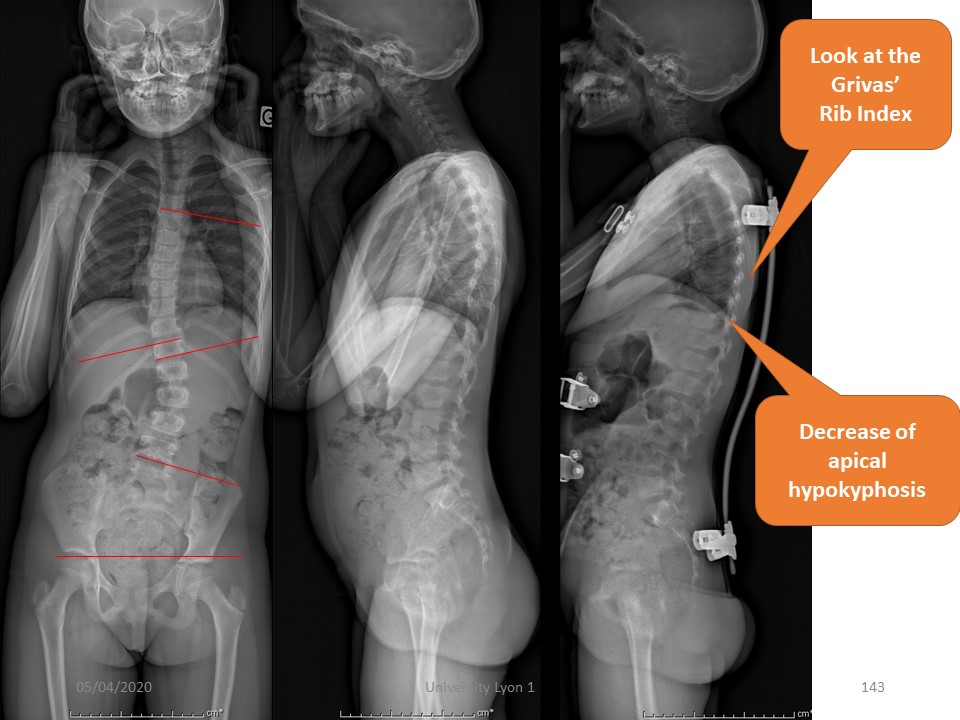

When the hyperkyphosis is associated with a frontal deviation, the ARTbrace remains the ideal brace. It controls both scoliosis and kyphosis. In brace, correction of scoliosis is total, and correction of kyphosis partial. |

But the correction in the sagittal plane will continue throughout the treatment with, at the end of treatment, restoration of almost physiological curvatures. |

In this 10-year-old patient, scoliosis is associated with a flat back. |

In the ARTbrace, scoliosis and pelvic rotation are well corrected. |

In the sagittal plane, a quasi-physiological thoracic kyphosis is restored. |